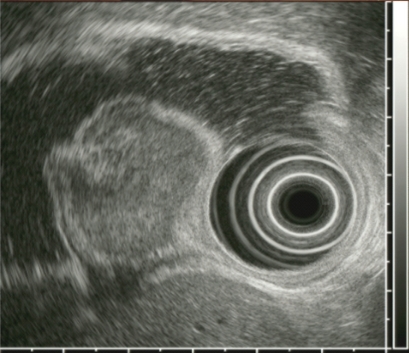

Figure 2

Endoscopic ultrasound revealed an about 29 × 25-mm inhomogeneously hypoechoic protruding mass in the submucosal layer.

A 44-year-old woman was referred for endoscopic ultrasound (EUS) evaluation of a gastric submucosal tumor that was found during a health checkup. At endoscopy, a tulip-like mass with a central lobulated dent was found in the upper body of the stomach (Fig. 1). A biopsy disclosed only dilated blood vessels in edematous stroma. EUS revealed a 29 × 25-mm inhomogeneously hypoechoic protruding mass in the submucosal layer (Fig. 2). Contrast-enhanced computed tomography revealed a high-enhancing submucosal mass in the stomach with no metastatic lesions. A laparoscopic wedge resection was done. The resected tumor had ribbon-like patterns of uniform cells with round nuclei and pink cytoplasm, confined mainly to the submucosa (Fig. 3A). Immunohistochemically, the tumor cells were stained with synaptophysin (Fig. 3B). The mass was diagnosed as a gastric carcinoid tumor. This patient has been followed for 2 years with no evidence of recurrence.